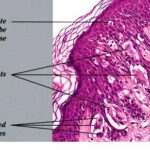

Unlike ordinary nevi and melanomas, melanocytic cells in Spitz nevi are large—often twice the size of epidermal basal keratinocytes, with prominent mononuclear or multinucleated giant cells in the epidermis and/or dermis . Mitoses, usually few in number, are detected in one-half the cases, whereas atypical mitoses are uncommon in Spitz nevi. In contrast to melanoma, the melanocytic cells in Spitz nevi show progressive maturation with increasing depth, becoming smaller and more similar to ordinary nevomelanocytes, with the overall distribution of cells in the dermis being wedge-shaped, with narrowing of the wedge toward the subcutaneous fat.

Coalescent eosinophilic globules (Kamino bodies), periodic acid-Schiff-positive and diastase-resistant (resembling colloid bodies), have been reported in 60 percent of Spitz nevi. Similar globules may be detected in 2 percent of melanomas and 0.9 percent of typical acquired nevi, but the globules are smaller in size, more difficult to find, single rather than coalescent, and commonly periodic acid-Schiff-negative.

Melanocytic elements are usually arranged in well-circumscribed nests, although there may be permeation of the epidermis by single cells or small groups of cells. In those cases with epidermal nests, artifactual clefts are usually seen above the nests in half the cases, a finding rarely observed in melanoma. The epidermis is usually hyperplastic, with elongated and bulbous pegs and knobs extending into the dermis, although thinning and even ulceration may occur rarely. The dermal inflammatory cell infiltrate may be slight or marked, band-like, and mainly at the base or patchy around blood vessels and/or intermixing with tumor cells. Although melanin was observed in all 13 patients originally described by Spitz, more recent studies have determined that melanin was moderate in 10 percent of cases and heavy in 5 percent.88